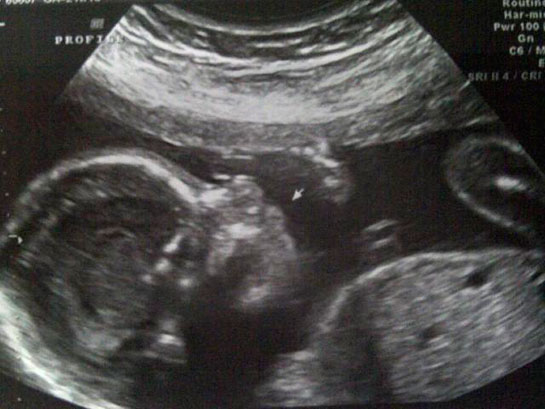

| 36 haftalık gebelik, bir hamilelik sürecinin önemli bir aşamasını temsil eder. Bu dönem, fetüsün gelişiminde kritik bir dönemdir ve anne adayının sağlığı bakımından da dikkate alınması gereken birçok faktör vardır. Bu makalede, 36 haftalık gebelik sürecinin özellikleri, anne adayı ve fetüs üzerindeki etkileri ile birlikte, bu dönemde dikkat edilmesi gereken konular ele alınacaktır. Fetüs Gelişimi 36 haftalık gebelikte fetüs, doğuma oldukça yakın bir dönemde bulunmaktadır. Bu aşamada fetüsün gelişimi ile ilgili bazı önemli noktalar şunlardır:

36 haftalık gebelik sürecinde yaşadıklarım gerçekten çok ilginç. Bebeğimin boyunun 47 cm ve ağırlığının 2 kg 700 gram olması beni heyecanlandırıyor. Her gün ortalama 30 gram alması da bu süreçteki gelişimini gösteriyor. Bebeğin doğuma hazırlandığını bilmek güzel ama bu haftayı atlatmanın verdiği rahatlıkla birlikte üzerimdeki yükün biraz hafiflemesi de sevindirici. Hormonal değişimler nedeniyle bedenimdeki gevşeme ve yumuşama beni yavaşlatıyor. Yürüyüşlerim değişti, bu da normal. Ancak bel ve pelvisteki ağrılar beni rahatsız ediyor. Yemek yeme konusunda da sıkıntılar yaşıyorum, bebeğim artık çok yer kaplıyor. Küçük porsiyonlarla beslenmek zorundayım. Mide yanmamın hafiflemesi, nefes almamı kolaylaştırdı ama bebeğim aşağı doğru inmeye çalıştıkça alt karın bölgesinde baskı hissediyorum, bu da rahatsız edici. Braxton Hicks kasılmalarının daha fazla hissedilmesi de dikkatimi çekiyor. Doğum sancılarının başlaması için her an hazırlıklı olmam gerektiğini biliyorum. Bebeğimin hareketlerinde azalma olursa ya da vajinal kanama yaşarsam hemen doktora gitmem gerektiğini unutmayacağım. Vajinal akıntıdaki artış beni endişelendiriyor ama cinsel birliktelikten sonra lekelenmenin normal olduğunu öğrenmek biraz olsun rahatlatıyor. Karın kaşıntım da dayanılmaz hale geldi; badem yağı ve E vitamini kremleri kullanmaya başladım. Uyku sorunlarıyla başa çıkmak için rahat kıyafetler giymek zorundayım. Ayaklarımda ve bileklerimdeki şişlik beni oldukça rahatsız ediyor fakat bol sıvı tüketmeye dikkat ediyorum. Halsizlik hissi normal ama doğumun yaklaşmasıyla birlikte bir enerji patlaması yaşıyorum. Artık tuvalet ihtiyacım da arttı, bu durum da yeni bir alışkanlık haline geldi. Tüm bu süreç gerçekten hem zorlu hem de heyecan verici!